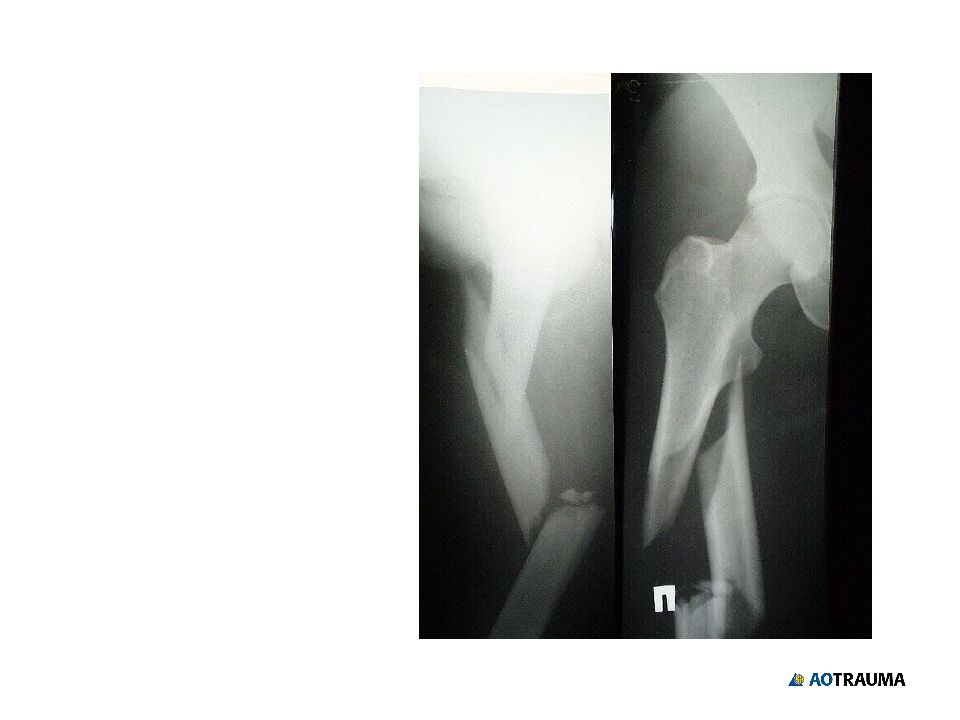

Слайд 22: Проксимальный сегмент бедренной кости

А В С Околосуставной или суставной? внекапсульный или внутрикапсульный?

Изображение слайда